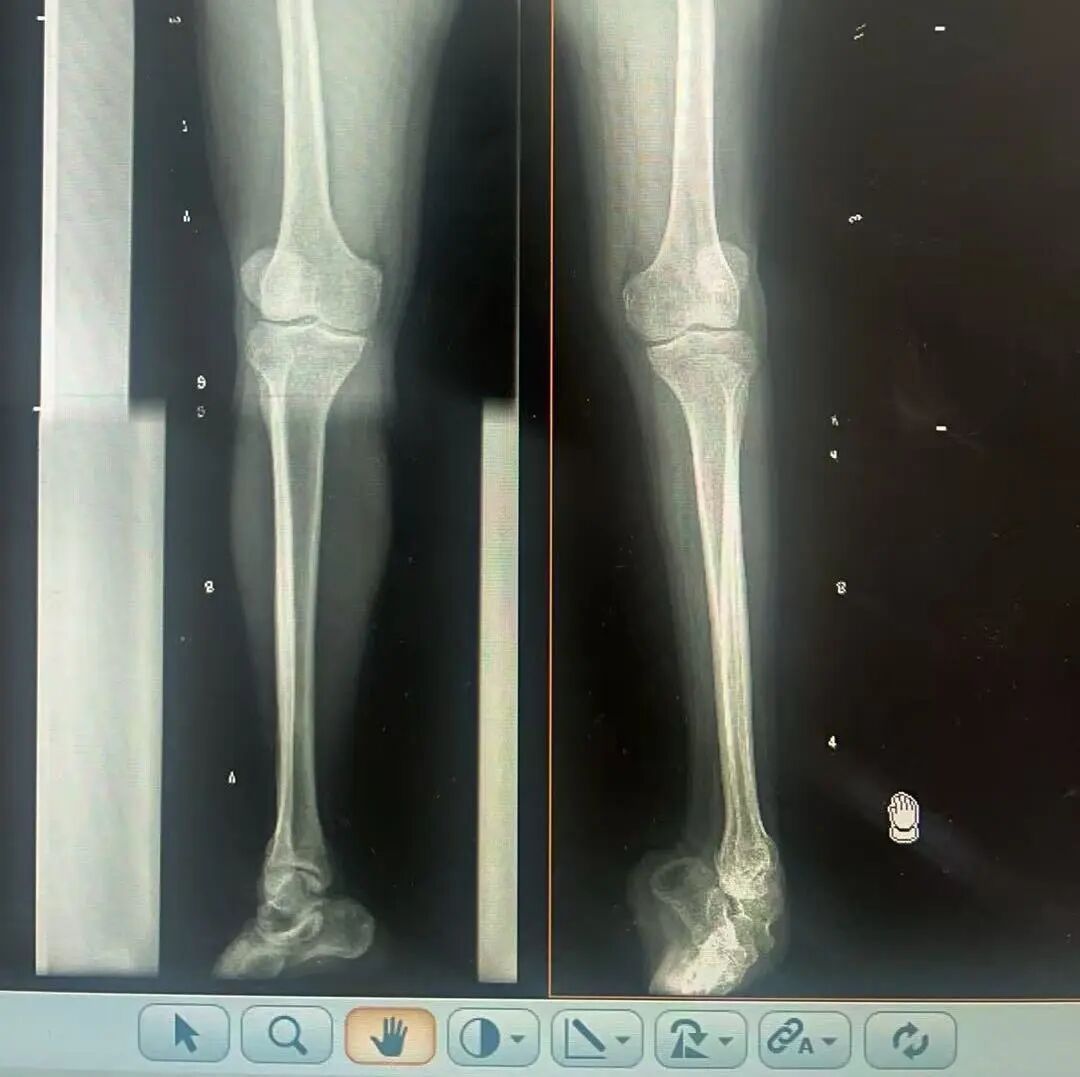

術前X光片 VS 術后治療效果

骨科隨即為陽先生進行了全面的檢查。診斷明確而復雜:陽先生患有脊髓灰質炎后遺癥、左踝馬蹄內翻足、骨盆傾斜……面對這張沉甸甸的診斷書,由肢體功能重建顯微修復學科組長鄭群龍所帶領的醫(yī)療團隊沒有畏懼,“這是一個家庭38年的堅守與期盼,我們必須全力以赴”

針對陽先生的復雜情況,鄭群龍醫(yī)師團隊制定了詳盡的手術方案:左踝關節(jié)融合+馬蹄足畸形矯正+跟腱延長+外固定架固定術。手術的核心,正是伊里扎洛夫技術。這項技術如同精密的“時空建筑學”,通過微創(chuàng)安裝環(huán)形外固定架,前足-后足安裝鋼環(huán),再將足的鋼環(huán)與脛骨的固定鋼環(huán)在踝關節(jié)前、后、左、右用帶關節(jié)的螺紋桿連接,由此構建成一個能體外牽拉調控的三維立體構型,在術后進行精準、緩慢的調整,一寸一寸逐步將畸形的骨骼、軟組織恢復到正常位置。

9月1日,在全麻狀態(tài)下,陽先生接受了伊里扎洛夫外固定架安裝術。鄭群龍團隊在陽先生左足足踝部植入克氏針及半針,安裝外固定架,通過支架的機械結構對馬蹄內翻畸形進行緩慢、持續(xù)的牽拉矯正。術后,鄭群龍團隊反復指導訓練陽先生父子進行外固定架的日常調試,按照預定計劃每日調整螺桿,逐漸糾正足部畸形,并配合專業(yè)的康復訓練,包括踝關節(jié)主動及被動活動、下肢肌力訓練等項目促進陽先生腿部肢體功能恢復,預防肌肉萎縮及關節(jié)僵硬。